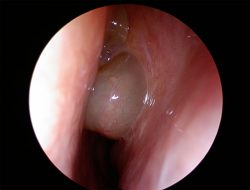

В медицине полипами называют патологический рост тканей над слизистой органов. Существует 2 вида: с широким основанием (без ножки) и имеющий ножку (растет на стебельке). Вырастает почти на всех органах, имеющих слизистую: желудок, кишечник, шейка матки, в носу (аденоиды), желчном и мочевом пузырях, бронхах и легких, во рту. Образование доброкачественное и в онкозаболевания перерождается редко. Всегда неправильной формы и чаще всего по виду напоминает каплю. Причиной возникновения становятся:

“Излюбленное” место для полипа – слизистые оболочки.

Существует 3 вида полипов: неопластический (наиболее опасный, поскольку перерождается в злокачественную опухоль), воспалительный (вырастает только на очагах воспаления) и гиперпластический (когда здоровая слизистая патологически разрастается). Полипы растут бессимптомно и долгое время не дают о себе знать. Однако позднее признаки полипоза появляются. В зависимости от пораженного органа, симптомы полипов такие: